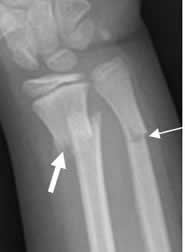

Fig 33. Compromiso de las corticales.

Rx AP. Fractura completa en el radio distal (Flecha gruesa) e incompleta en el cubito distal. (Flecha delgada).